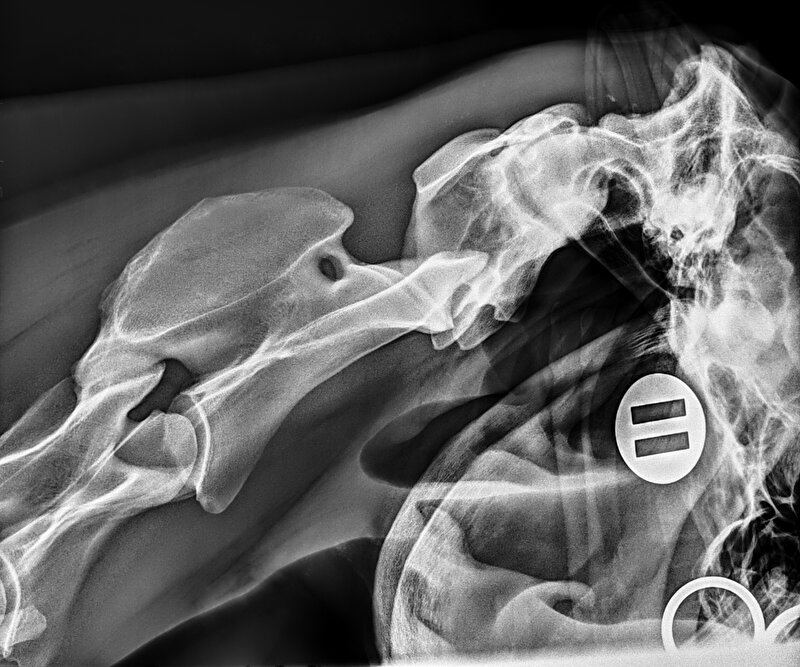

Tijdens de aankoopkeuring van een nieuw paard was op de rontgenfoto's van de nek lichte mineralisatie van de occiput (achterhoofdsknobbel) zichtbaar. De dierenarts zou het paard hier niet op afkeuren maar het is wel een bemerking.

Afbeelding

Dit is de rontgenopname